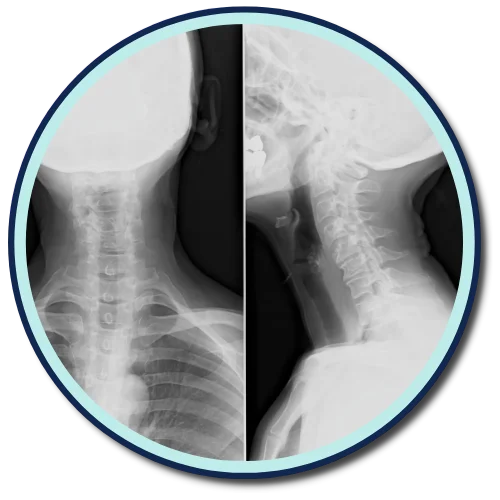

CLINIC* uses the Gonstead method of adjusting and analyzing the spine. We're one of a few offices in CITY* that exclusively uses the Gonstead method. By thoroughly analyzing the spine through the use of x-ray, instrumentation, visualization, static and motion palpation you can expect a properly delivered adjustment.